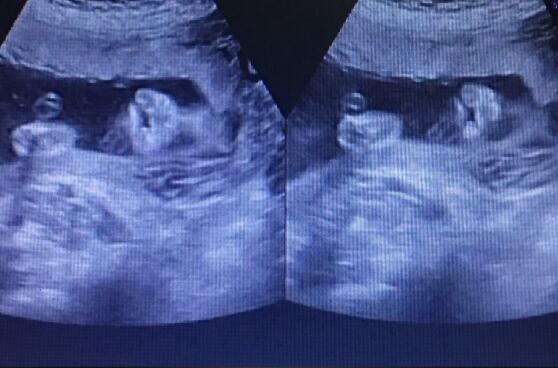

5月12日,正值母親節(jié),本是象征著愛意和美好的一天,但孕21周的二胎孕媽黃女士在武漢仁愛醫(yī)院做四維大排畸檢查時(shí)卻收到了一個(gè)晴天霹靂。 胎兒嘴唇上有裂縫,為唇裂。···